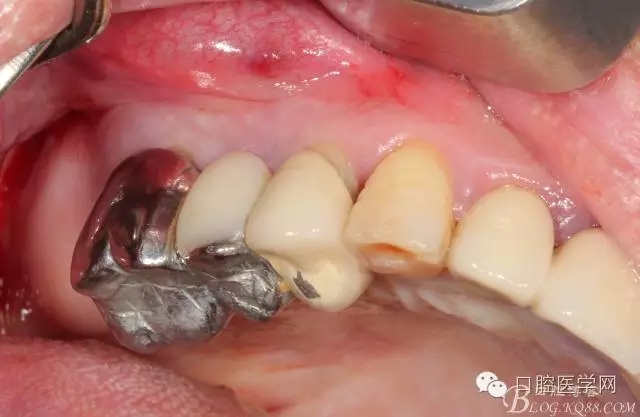

牙周治療以后過了段時間我們開始拔牙種牙,上圖是牙周治療以后開始種牙的口內(nèi)照片,效果還是有的。

拔掉以后(這樣能夠整體拔出 說明這組牙是非常松動了)

拔牙以后 拔牙窩少許肉芽 發(fā)現(xiàn)13遠中還是有些肉芽的

簡單清理以后 (一般這種情況我是不太翻瓣的 )這個患者我在清理13遠中時候我發(fā)現(xiàn)有些肉芽而且超過了我的預期的量,我開始不太淡定了 。 我在想牙周科同事是不是知道我要拔牙,沒有在14 16 牙位用洪荒之力刮治啊。結(jié)果我翻瓣一點點去檢驗了下牙周科刮治的效果,那么結(jié)果是非常好,沒啥太多的肉芽,不翻瓣完全可以刮干凈,看來我得信任我的同事啊,牙周科非常給力。13牙位遠中的肉芽估計的確不好刮掉,所以留給我刮了吧。